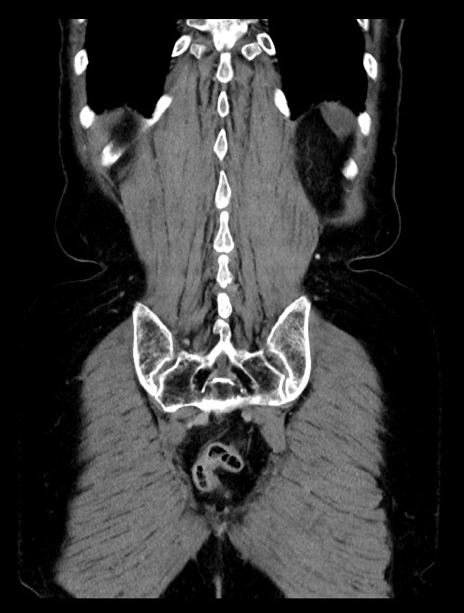

横断像

症例23(冠状断像)

【症例】70歳代女性

【主訴】下腹部痛・嘔吐

【現病歴】2日前より腹痛あり。昨日嘔吐あり。症状改善しないため来院。

【既往歴】胃GISTに対して胃部分切除後。

【身体所見】BT 37.1℃、BP 128/77mmHg、腹部:平坦・軟、下腹部に圧痛あり。

【データ】WBC 10200、CRP 0.31